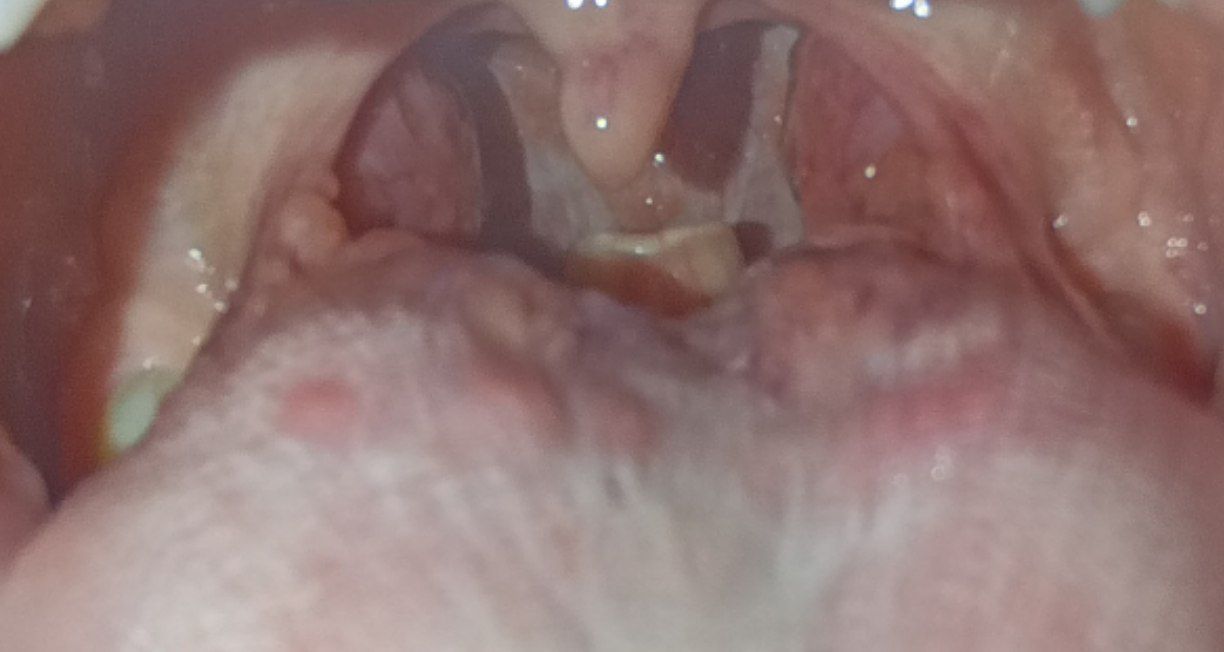

Нормальное ли горло?